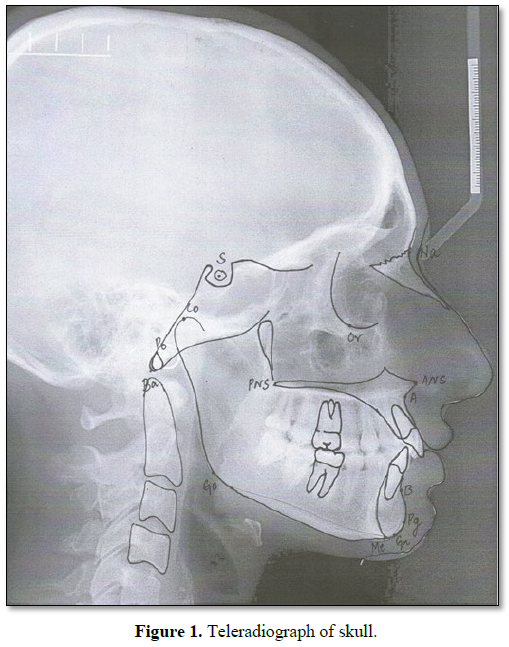

The patients excluded from this study were those undergoing any long-term systemic therapy for severe chronic diseases (except AIDS in study group) who had received earlier radiotherapy, chemotherapy or any previous orthodontic as well as orthopedic treatment. The diagnostic aids for orthodontic documentation were facial photographs, panoramic radiograph, lateral teleradiograph and study models. For this study, we used only teleradiographs, on which cephalometric points of hard profile were identified and used for measuring craniofacial morphology. Cephalometric tracings of eighteen (linear and angular) measurements on teleradiographs were done by using 2 methodologies. The mean values of each measurement were compared between the two groups by age range. Overall, 14 points and 18 (linear and angular) measurements were used, all based on the previous studies by various authors [27-34] (Figure 1 and Table 1).